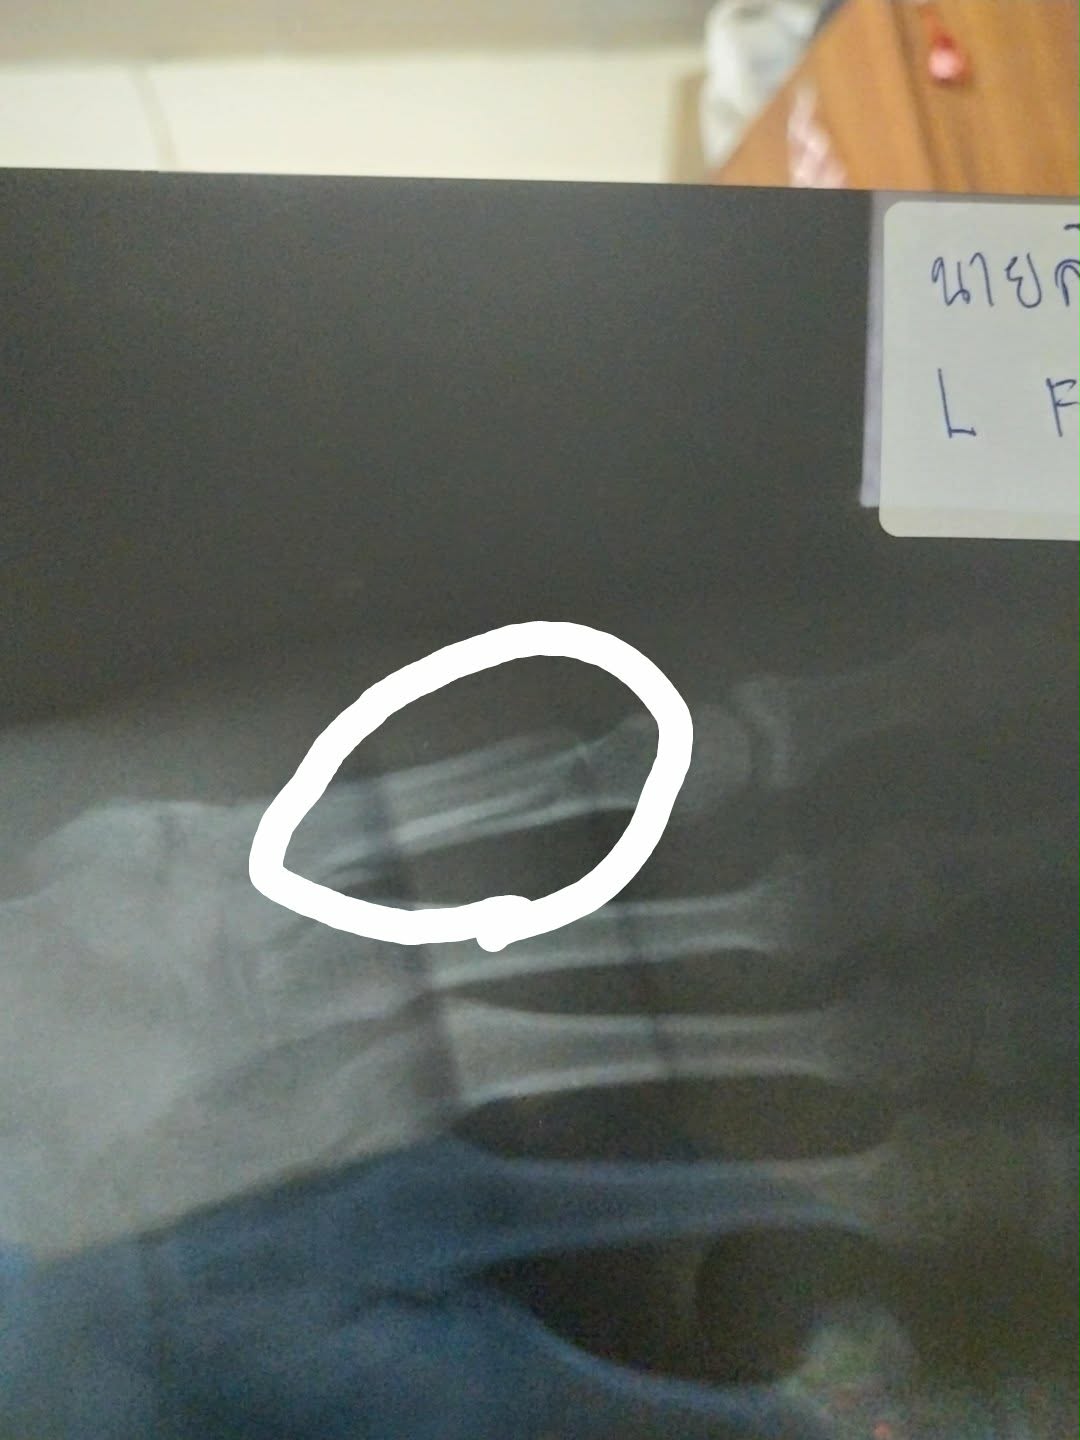

กระดูกหัก รักษาอย่างไรดี

กระดูกหัก ผ่า - ไม่ผ่า อย่างไหนดีกว่ากัน

กระดูกหักเมื่อไรจะหาย

กระดูกเท้าหักสามารถเดินลงส้นเท้าได้ไหม

แล้วถ้าเดินจะมีผลต่ออะไรไหมคะ กระดูกจะติดไหมคะ